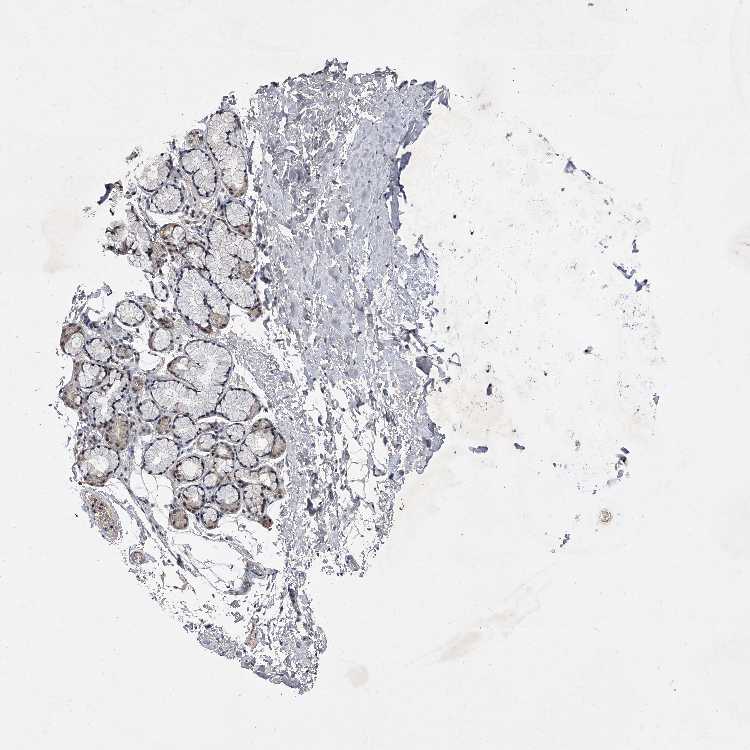

ADIPOSE TISSUE - Antibody stainingi

Antibody staining in the annotated cell types in the current human tissue is reported as not detected, low, medium, or high, based on conventional immunohistochemistry profiling in selected tissues. This score is based on the combination of the staining intensity and fraction of stained cells.

Each image is clickable and will lead to virtual microscopy that enables deeper exploration of all samples and also displays staining intensity scores, fraction scores and subcellular localization as well as patient and tissue information for each sample.

Antibody HPA030090Antibody HPA030091

Adipocytes LowNot detected